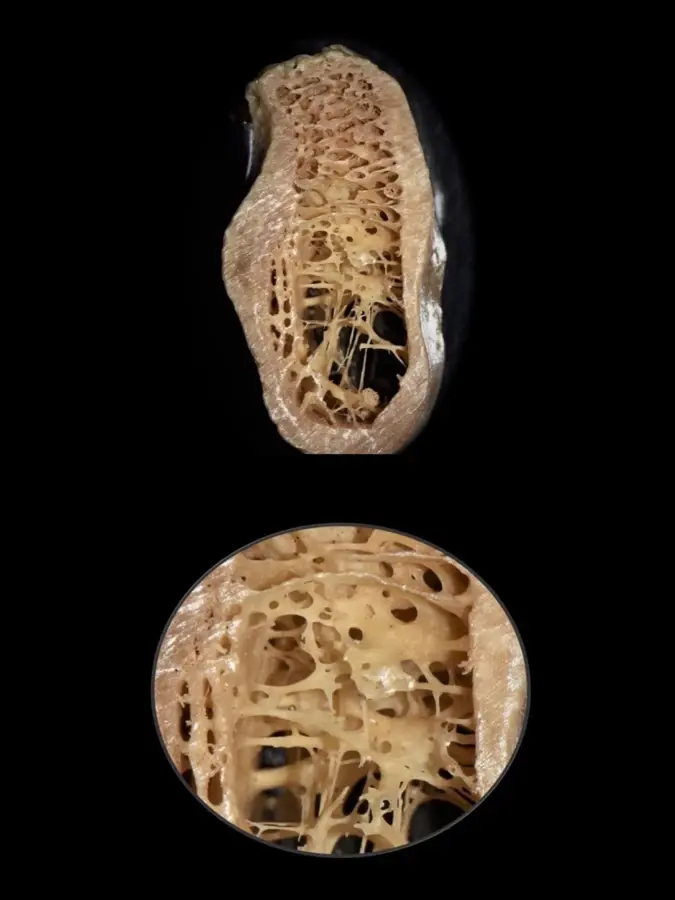

Durante años, se establecieron las propiedades biomecánicas del hueso basándose únicamente en medidas a gran escala, pudiendo diferenciarse entre el hueso trabecular y el hueso cortical. Sin embargo, actualmente es posible un mayor análisis a nivel micrométrico que permite explorar entre los componentes orgánicos, tisulares, celular y moleculares. Es así que gracias a aproximaciones nanoestructurales se muestran asociaciones entre las propiedades biomecánicas y las calidades óseas, las que se pueden presentar tanto en el hueso cortical como en el trabecular de manera indistinta. En el cortical, el espacio poroso ocupa el 5-10%, mientras que en el trabecular se encuentra en el 30-90% del total de la estructura9 (Figura 1).

Los esquemas clásicos de clasificación se basan en la proporción relativa que existe entre el hueso cortical compacto y el hueso trabecular esponjoso.10,11 El hueso tipo I se considera el menos vascular y más homogéneo, el tipo II es una combinación de hueso cortical con cavidades medulares, el tipo III está predominantemente compuesto de hueso trabecular, y el tipo IV se describe como una corteza muy delgada con trabéculas de baja densidad.12 Incluso se han propuesto diferentes analogías entre los tipos de huesos y los tipos de madera; que van desde la madera tipo balsa hasta la tipo roble.13 Posteriormente, siguieron surgiendo clasificaciones utilizando el criterio cuantitativo;14 sin embargo, su valor diagnóstico sigue siendo cuestionable.15,16

Calidad ósea según la clasificación de Lekholm y Zarb (Figura 2).

- Tipo I: hueso compacto completamente homogéneo.

- Tipo II: capa gruesa de hueso compacto rodeando al hueso trabecular denso.

- Tipo III: capa delgada de hueso compacto rodeando al hueso trabecular denso.

- Tipo IV: capa delgada de hueso compacto rodeando al hueso trabecular poco denso.

En base a estudios realizados en biomodelos, consideramos que es importante, además de los clásicos parámetros, analizar el grosor de las trabéculas óseas y las dimensiones de los espacios medulares, ya que juegan un rol determinante en la calidad y dureza del hueso.

Las clasificaciones tradicionales asocian la calidad ósea con ciertos sectores en los maxilares

Por ejemplo, se dice que el sector anteroinferior de la mandíbula suele presentarse hueso tipo I y en el posteroinferior tipo II. La variante en la zona posterioinferior mandibular se debe a que, a pesar de tener una buena cortical ósea y cantidad de hueso esponjoso, la dimensión de los espacios medulares es muy amplia y el grosor de las trabéculas tan finas como el espesor de un cabello11 (Figura 3).